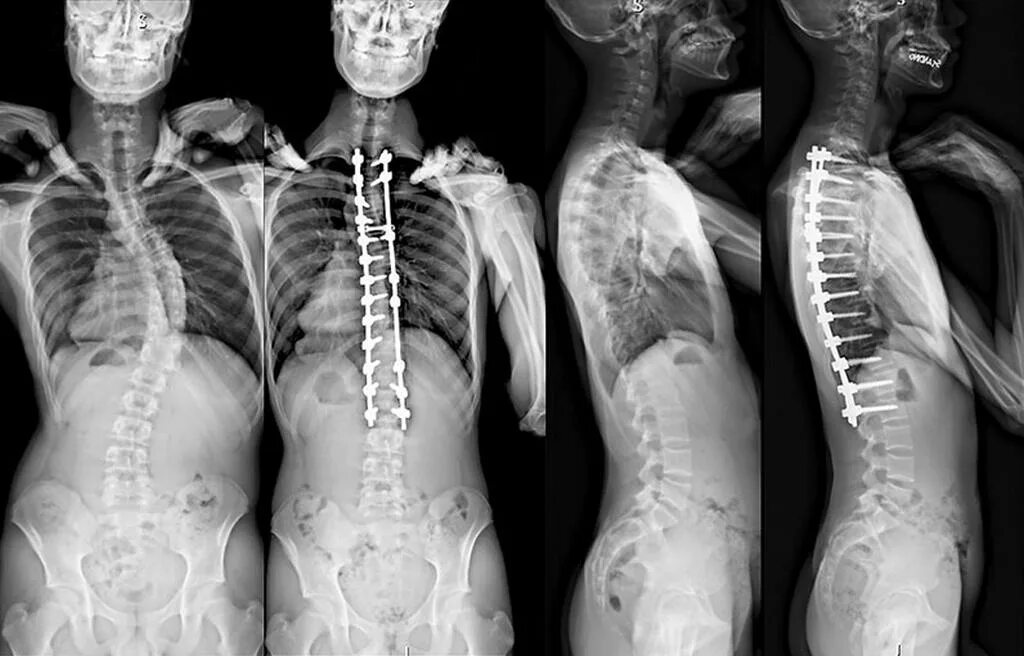

Сколиоз хирургия